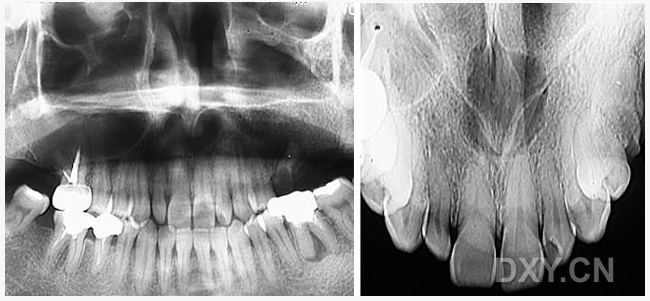

成釉細胞瘤

球狀上頜囊腫

含牙囊腫

球狀上頜囊腫    含牙囊腫